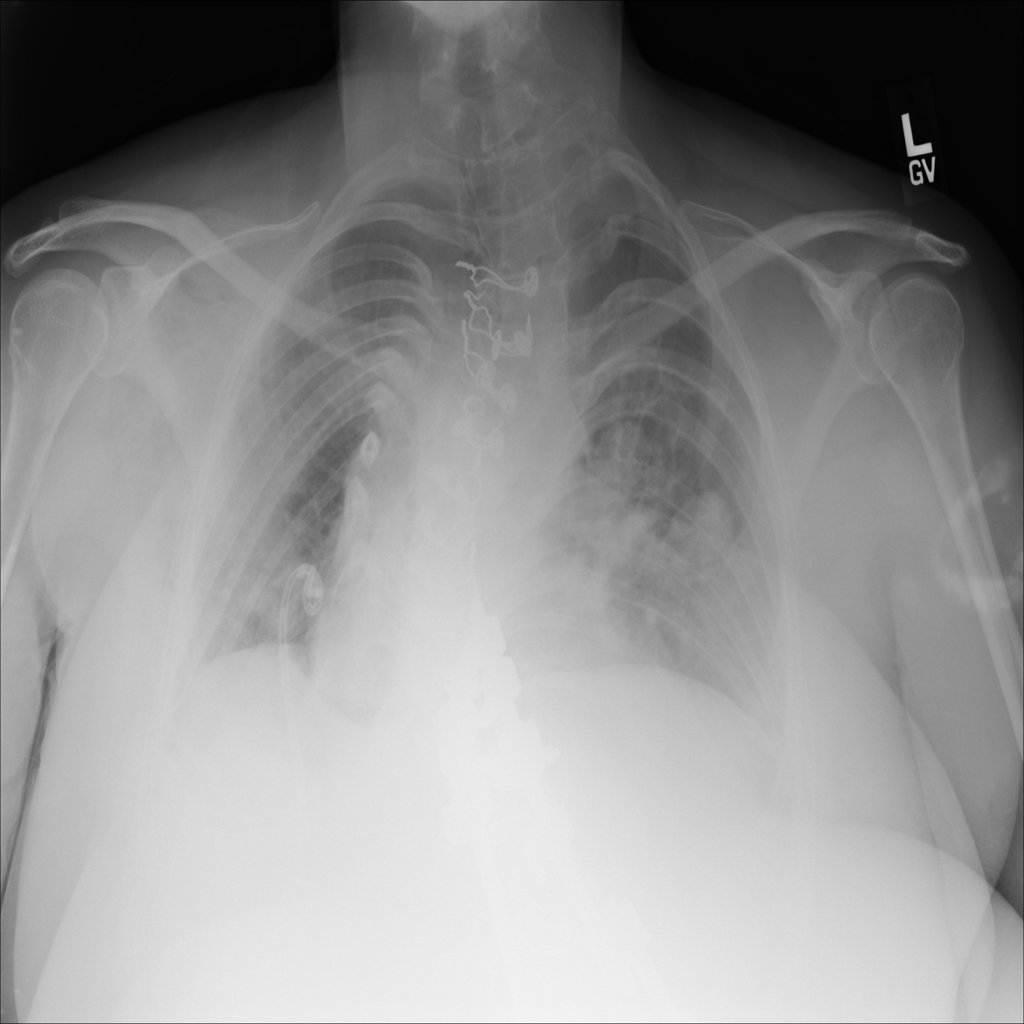

PAT-26A3 · IMG-008Nodule

PAT-26A3 · IMG-008

AP